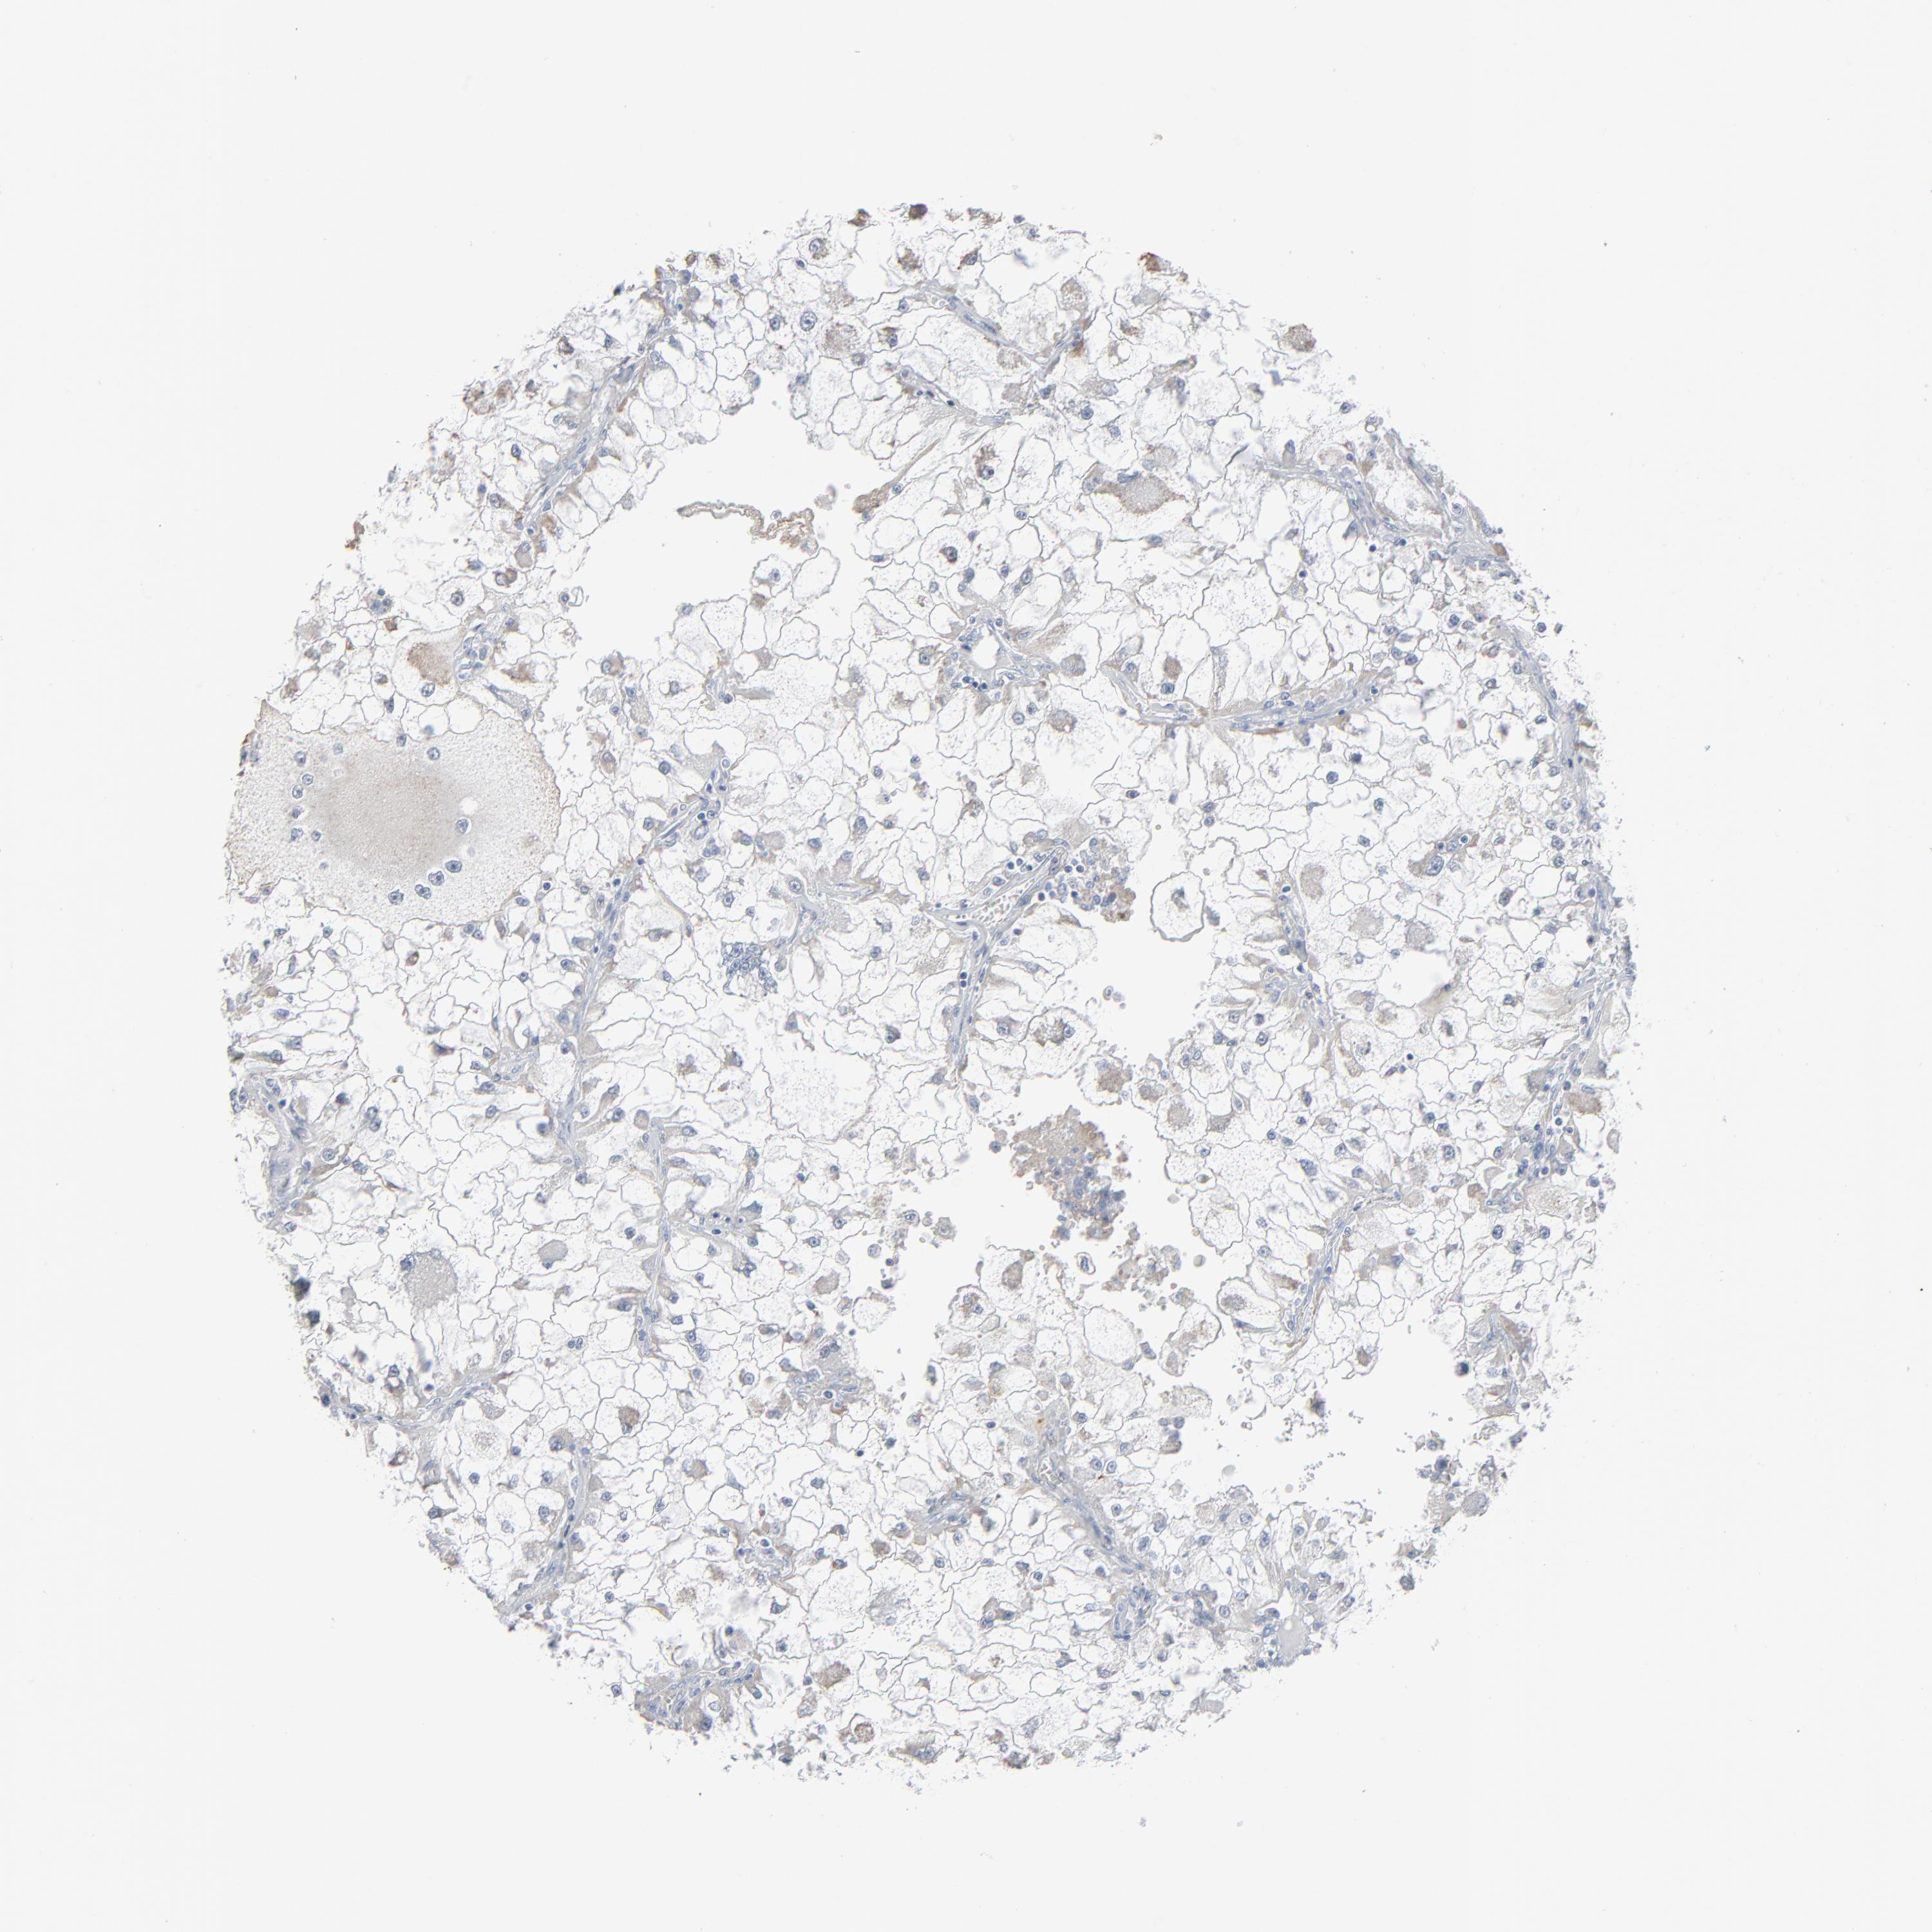

KIDNEY RENAL PAPILLARY CELL CARCINOMA (TCGA) - Interactive survival scatter ploti

The Survival Scatter plot shows the clinical status (i.e. dead or alive) for all individuals in the patient cohort, based on the same data that underlies the corresponding Kaplan-Meier plots. Patients that are alive at last time for follow-up are shown in blue and patients who have died during the study are shown in red.

The x-axis shows the expression levels (FPKM) of the investigated gene in the tumor tissue at the time of diagnosis. The y-axis shows the follow-up time after diagnosis (years). Both axes are complimented with kernel density curves demonstrating the data density over the axes. The top density plot shows the expression levels (FPKM) distribution among dead (red) and alive patients (blue). The right density plot shows the data density of the survived years of dead patients with high and low expression levels respectively, stratified using the cutoff indicated by the vertical dashed line through the Survival Scatter plot. This cutoff is automatically defined based on the FPKM cutoff that minimizes the p-score. The cutoff can be changed by dragging the vertical line or by entering a cutoff value in the square labeled "Current cut-off".

Under the Survival Scatter plot the p-score landscape (black curve; left axis) is shown together with dead median separation (red curve; right axis). Dead median separation is the difference in median mRNA expression between patients who have died with high and low expression, respectively. It is calculated as follows: median FPKM expression of dead patients with high expression - median FPKM expression of dead patients with low expression. This is intended to aid the user in visually exploring custom cutoffs and the associated p-scores and dead median separation.

Individual patient data is displayed and can be filtered by clicking on one or more of the category buttons on the top of the page. Categories describing expression level and patient information include: high, low, alive, dead, female, male and tumor stages. The scale of the x-axis can be toggled between linear and log-scale by clicking on the "x log" button. Mouse-over function shows TCGA ID, patient information and mRNA expression (FPKM) for each patient.

& Survival analysisi

Kaplan-Meier plots summarize results from analysis of correlation between mRNA expression level and patient survival. Patients were divided based on level of expression into one of the two groups "low" (under cut off) or "high" (over cut off). X-axis shows time for survival (years) and y-axis shows the probability of survival, where 1.0 corresponds to 100 percent.

PHGDH is not prognostic in Kidney Renal Papillary Cell Carcinoma (TCGA)

Best expression cut offi